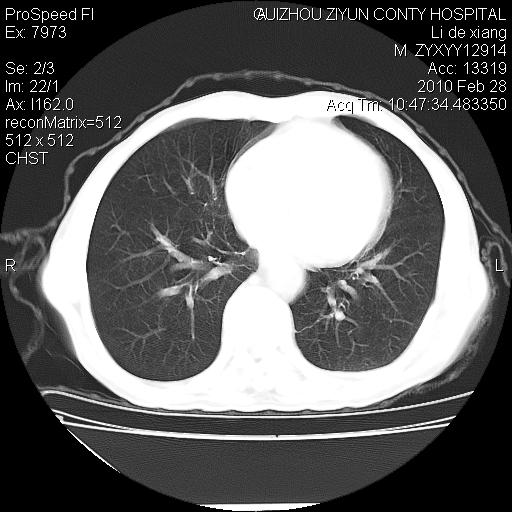

标题: CT24776:男 71Y 咳嗽咳痰胸痛两月,伴声音嘶哑。 [打印本页]

标题: CT24776:男 71Y 咳嗽咳痰胸痛两月,伴声音嘶哑。

左侧中央型肺癌伴左肺上叶阻塞性肺炎及节段性不张可能性大,建议纤支镜检查!

左侧中央型肺癌伴左肺上叶阻塞性肺炎及节段性不张可能性大,建议纤支镜检查!纵隔淋巴结转移.

左肺门部肿块,伴左上肺斑块影,周边模糊,支持左肺中央型肺癌伴节段性不张及阻塞性肺炎,结合支气管镜检查。

左上叶支气管狭窄,阻塞性病变,肺门肿块,纵隔及肺门淋巴结增大,中央性肺癌

左侧中央型肺癌伴左肺上叶阻塞性肺炎及纵隔淋巴结转移